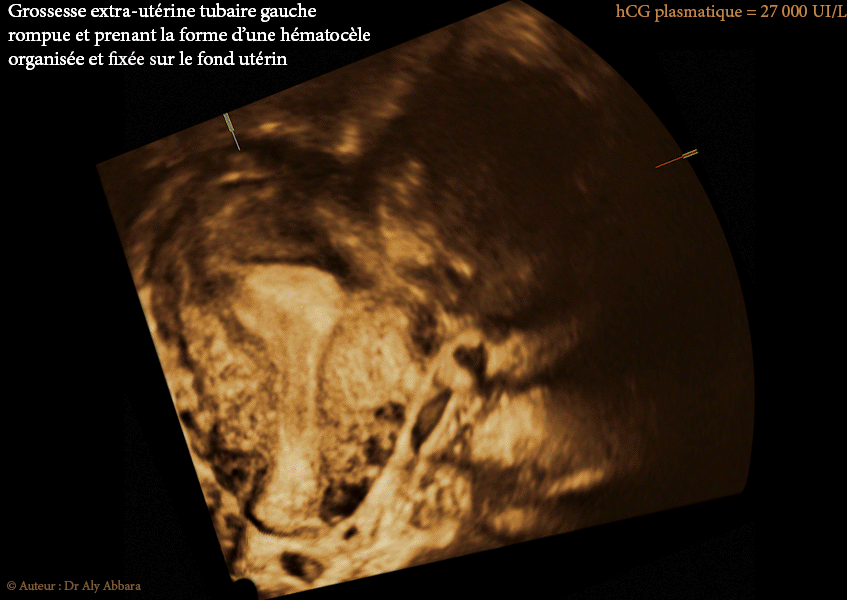

• Images échographiques puis cliniques peropératoires (format autodiaporama en GIFS animées) mettant en évidence la présence d'une grossesse extra-utérine tubaire gauche rompue et prenant la forme d’une hématocèle organisée et fixée sur le fond utérin et sur l'épiploon avoisinant :

• échographiquement, la masse fixée sur le fond utérin mesure 61 x 55 x 41 mm (ou environ 72 ml), elle est solide, hétéroéchogène avec vascularisation périphérique très limitée (il s'agit de la vascularisation propre à l'épiploon et au fond utérin, les deux organes sur lesquels cette masse organisée se fixe).

Ces caractéristiques échographiques laissent facilement confondre cette hématocèle avec un myome sous séreux fundique type 7 (classification FIGO 2011).

• aucune structure propre au sac gestationnel n'est identifiable ;

• hCG plasmatique = 27 000 UI/L